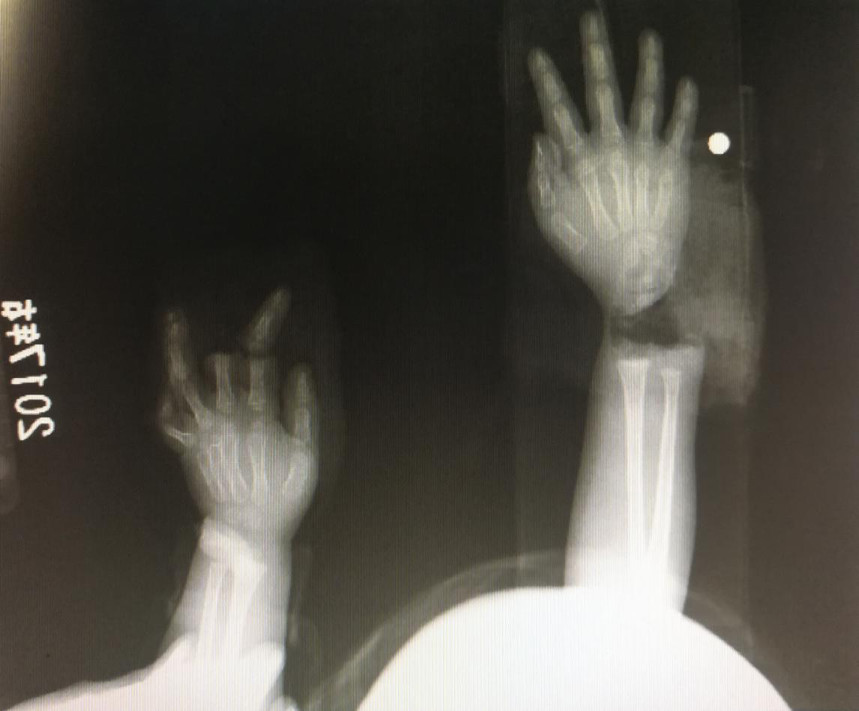

“急診在哪,急診在哪”,伴隨著一聲聲急促的問詢,一位年輕女士抱著渾身是血的小孩疾步前往急診室,懷里的小孩在疲憊與疼痛的交織下,時睡時醒。鑒于小孩的情況,急診醫生迅速安排給小孩拍了X光片,影像片結果顯示小孩左手手腕完全離斷,右手中、食指離斷,距離事發時間已經3個多小時,需盡快安排手術。

經過長達5個多小時的手術,小宇(化名)終于被送出了手術室,離斷的手腕和手指均已完成再植,但關于斷指的存活與否還需要經過一個十天的觀察期。小宇的主治醫生是長沙年輪骨科醫院手足外科馬思成醫生,據馬醫生介紹,小宇受傷情況比較嚴重,失血過多,而且兩個手都存在完全離斷的情況,手術時安排了兩組醫生同時進行,整個手術過程比較順利,目前小宇還處于觀察期。